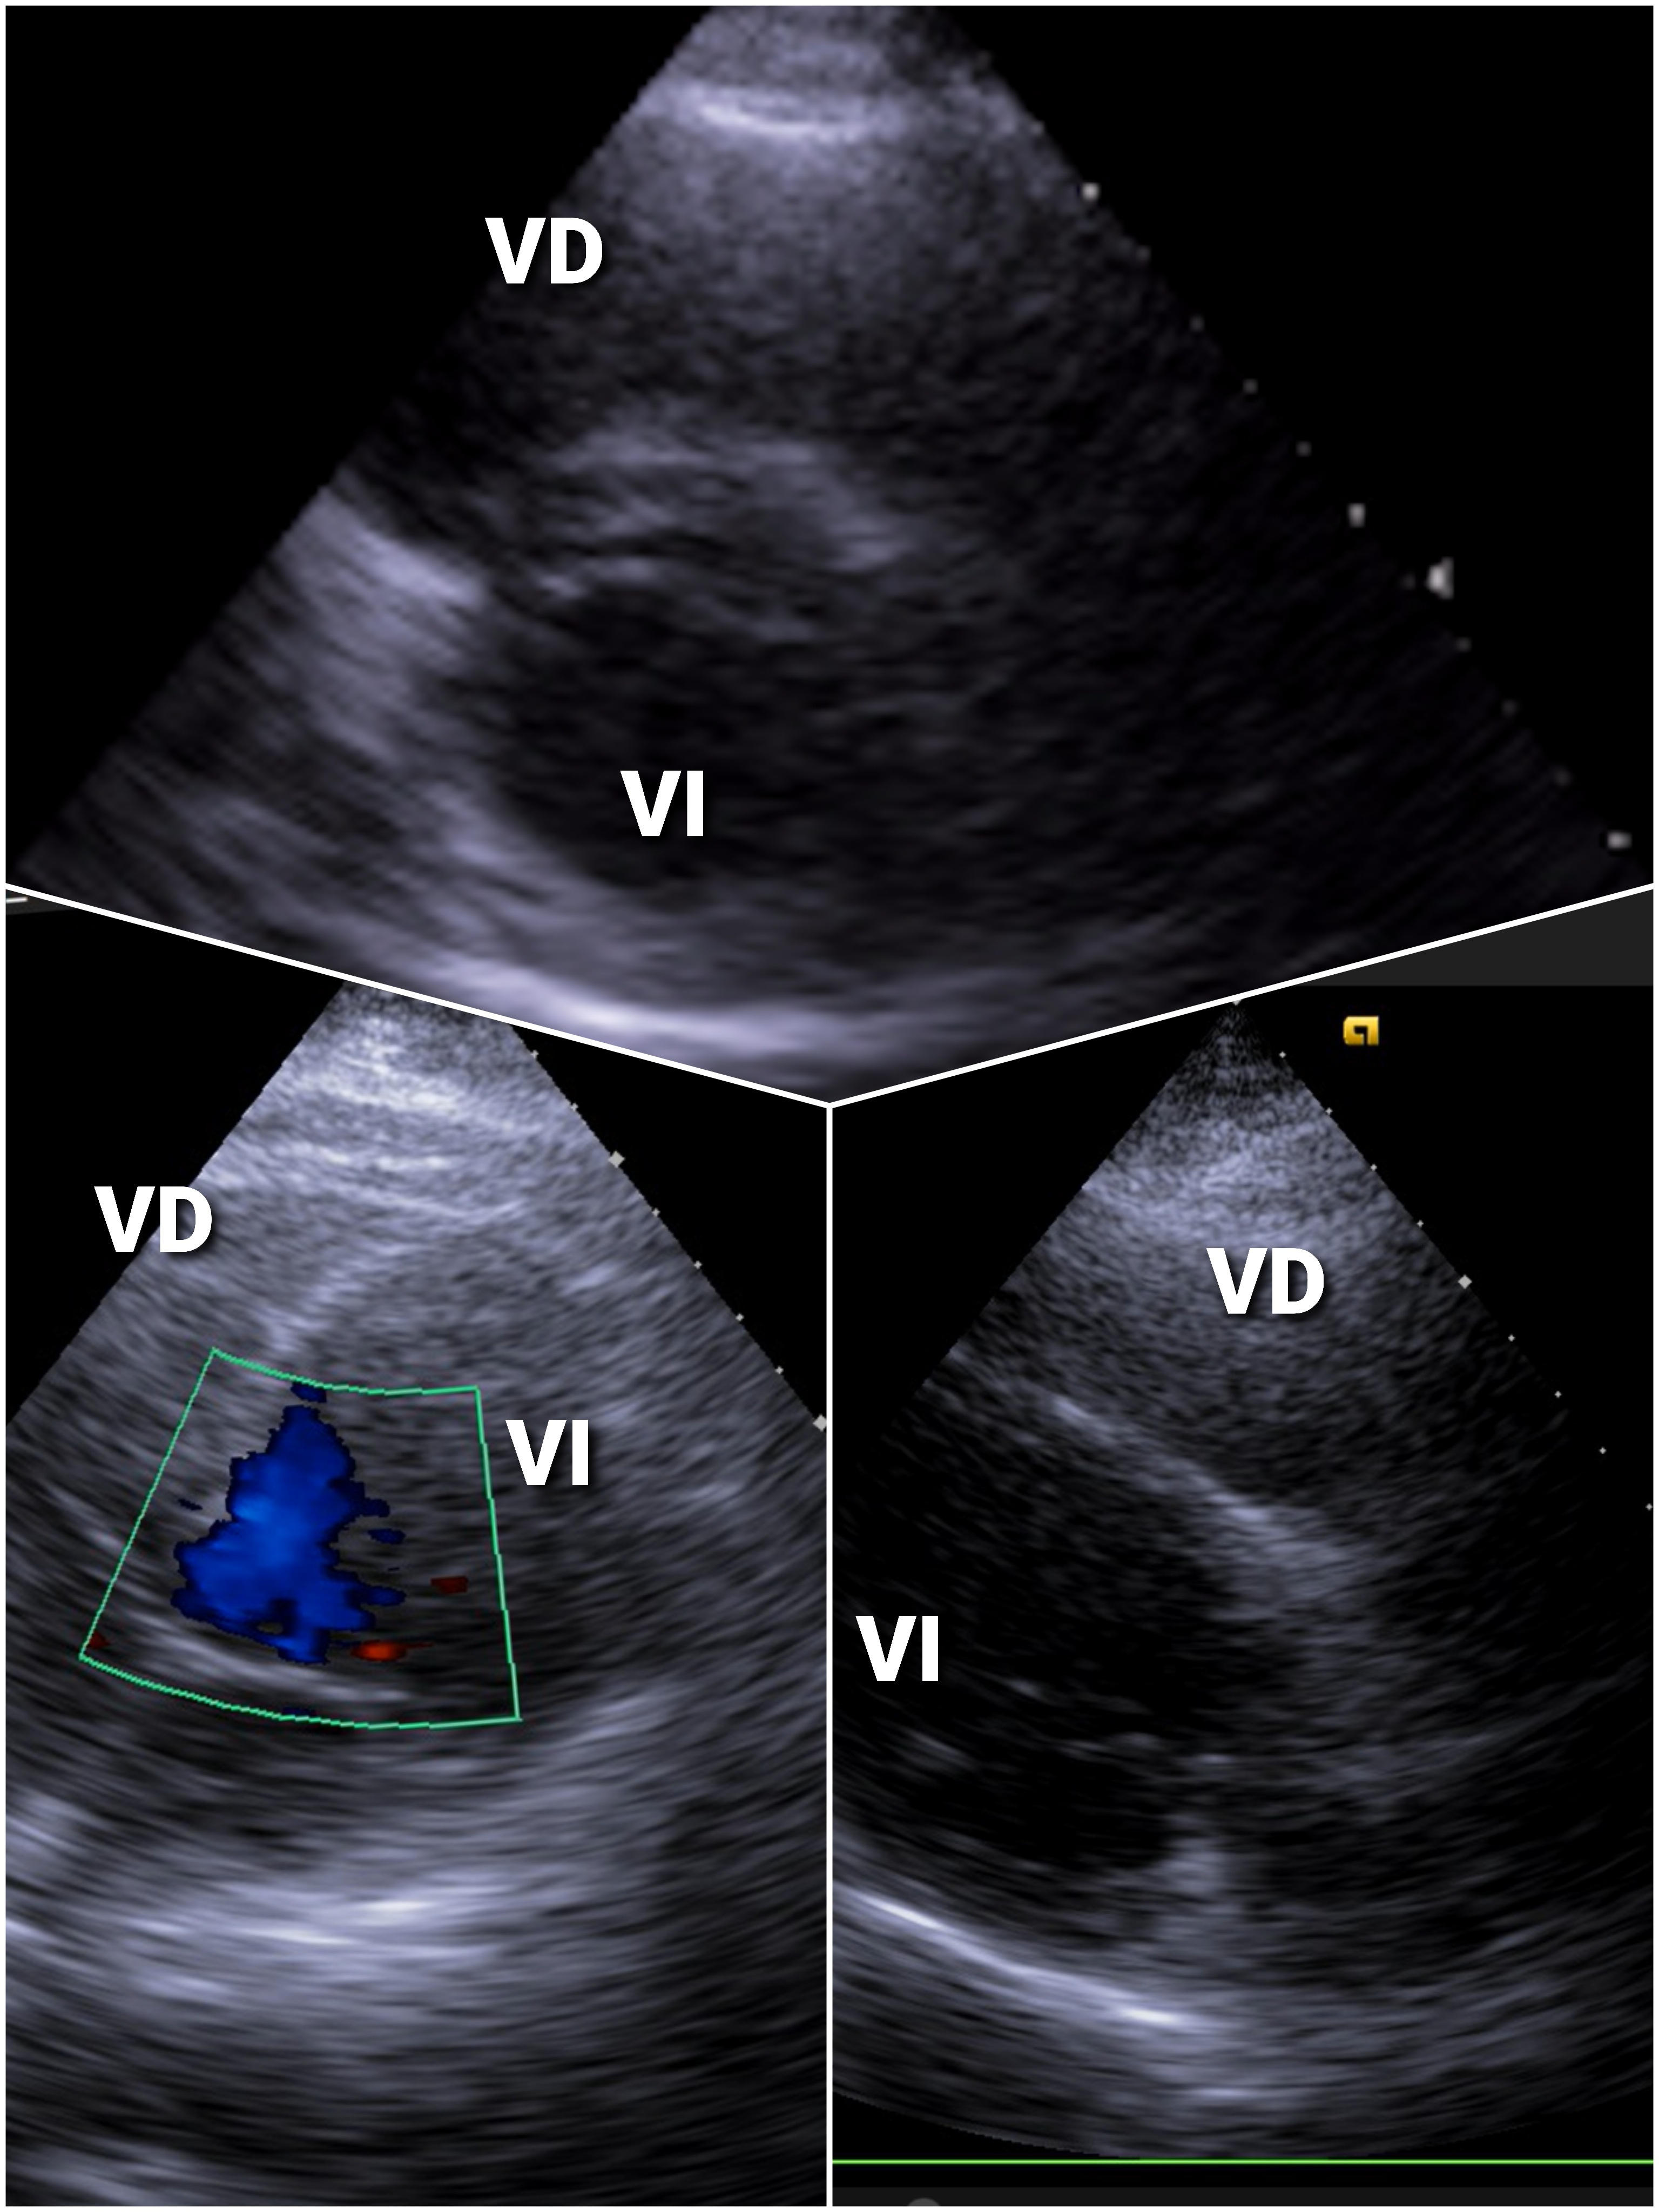

EcoCardioscopia: contractilidad preservada sinvalvulopa tías ni aumento de cavidades derechas.

Trombosis Venosa Profunda (TVP) Poplítea con sospecha de Embolismo Pulmonar (EP)

Si bién la ecografía permite el diagnóstico y seguimiento de la TVP desde Medicina de Familia, en este caso con dorsalgia derecha, disnea y caída de la saturación de O2 en decúbito, se deriva a Hospital por sospecha de EP. La gasometría arterial no descarta la presencia de EP. Un AngioTAC confirmaría o no la EP, importante para el diagnóstico y seguimiento del paciente.